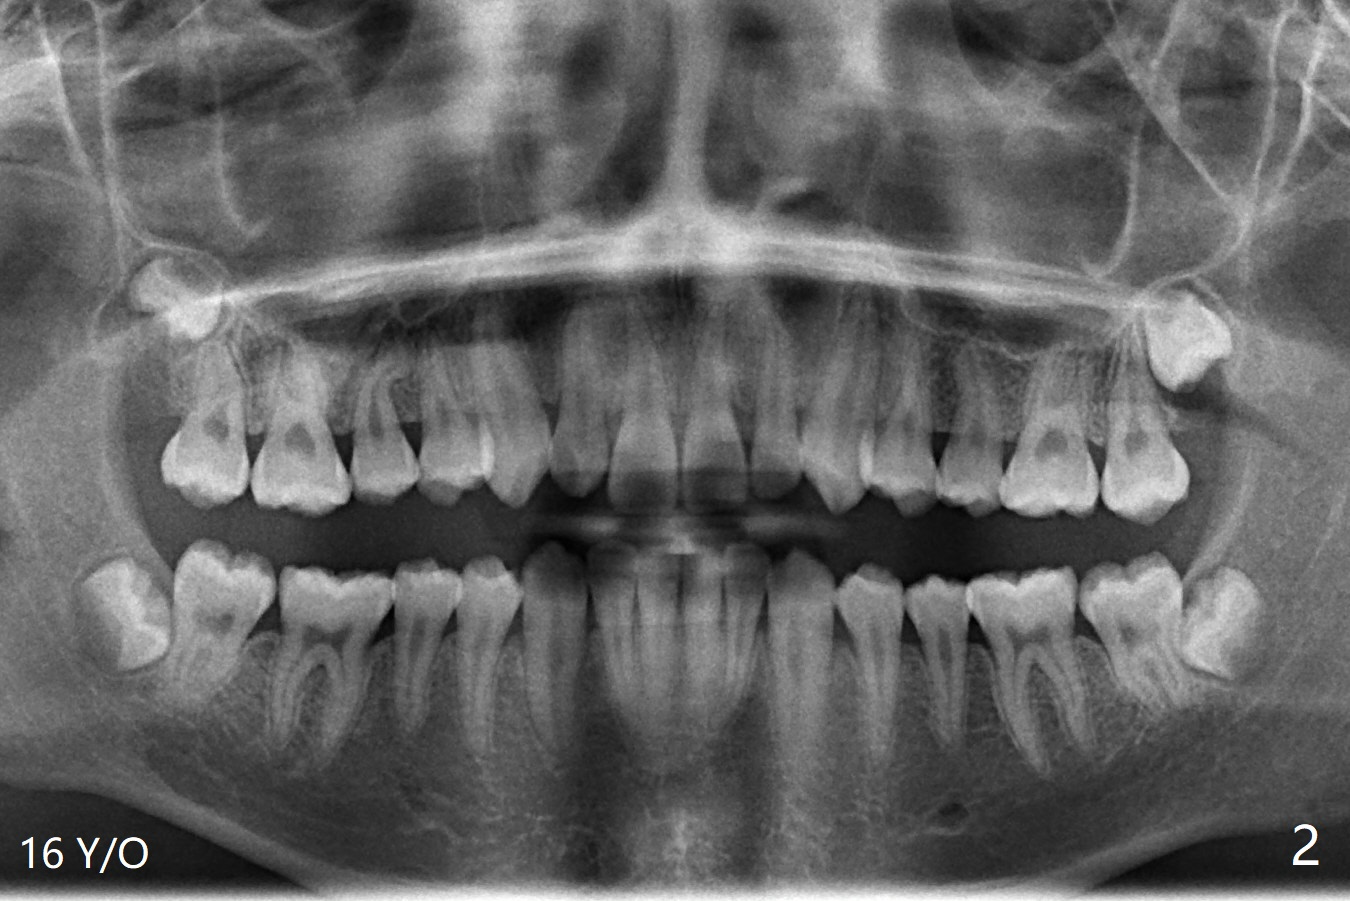

A 22-year-old man will return for 3rd molar extraction (4 of them, Fig.1-4). Prepare 2 or 3 #15 blades and 1-2 extra surgical burs. Since the third molars may overlap with the second ones, oblique incision (red line in Fig.4') will be mesial. Place Collagen and Osteogen plugs in the #32 and 17 sockets, respectively (Fig.4': C, O). As the roots are short and bone formation distal to the 2nd molars is critical, the plugs will be placed horizontally and coronally (Fig.4' white outline). No dovetail is needed. Pan 4 BW will be taken immediately and 3-4 months postop. The experiment will confirm whether collagen plug is enough to facilitate socket bone healing. In fact extraction of #1 turns out to be extremely difficult. There is not enough time for #16 and 17 extraction in one appointment (Fig.5).